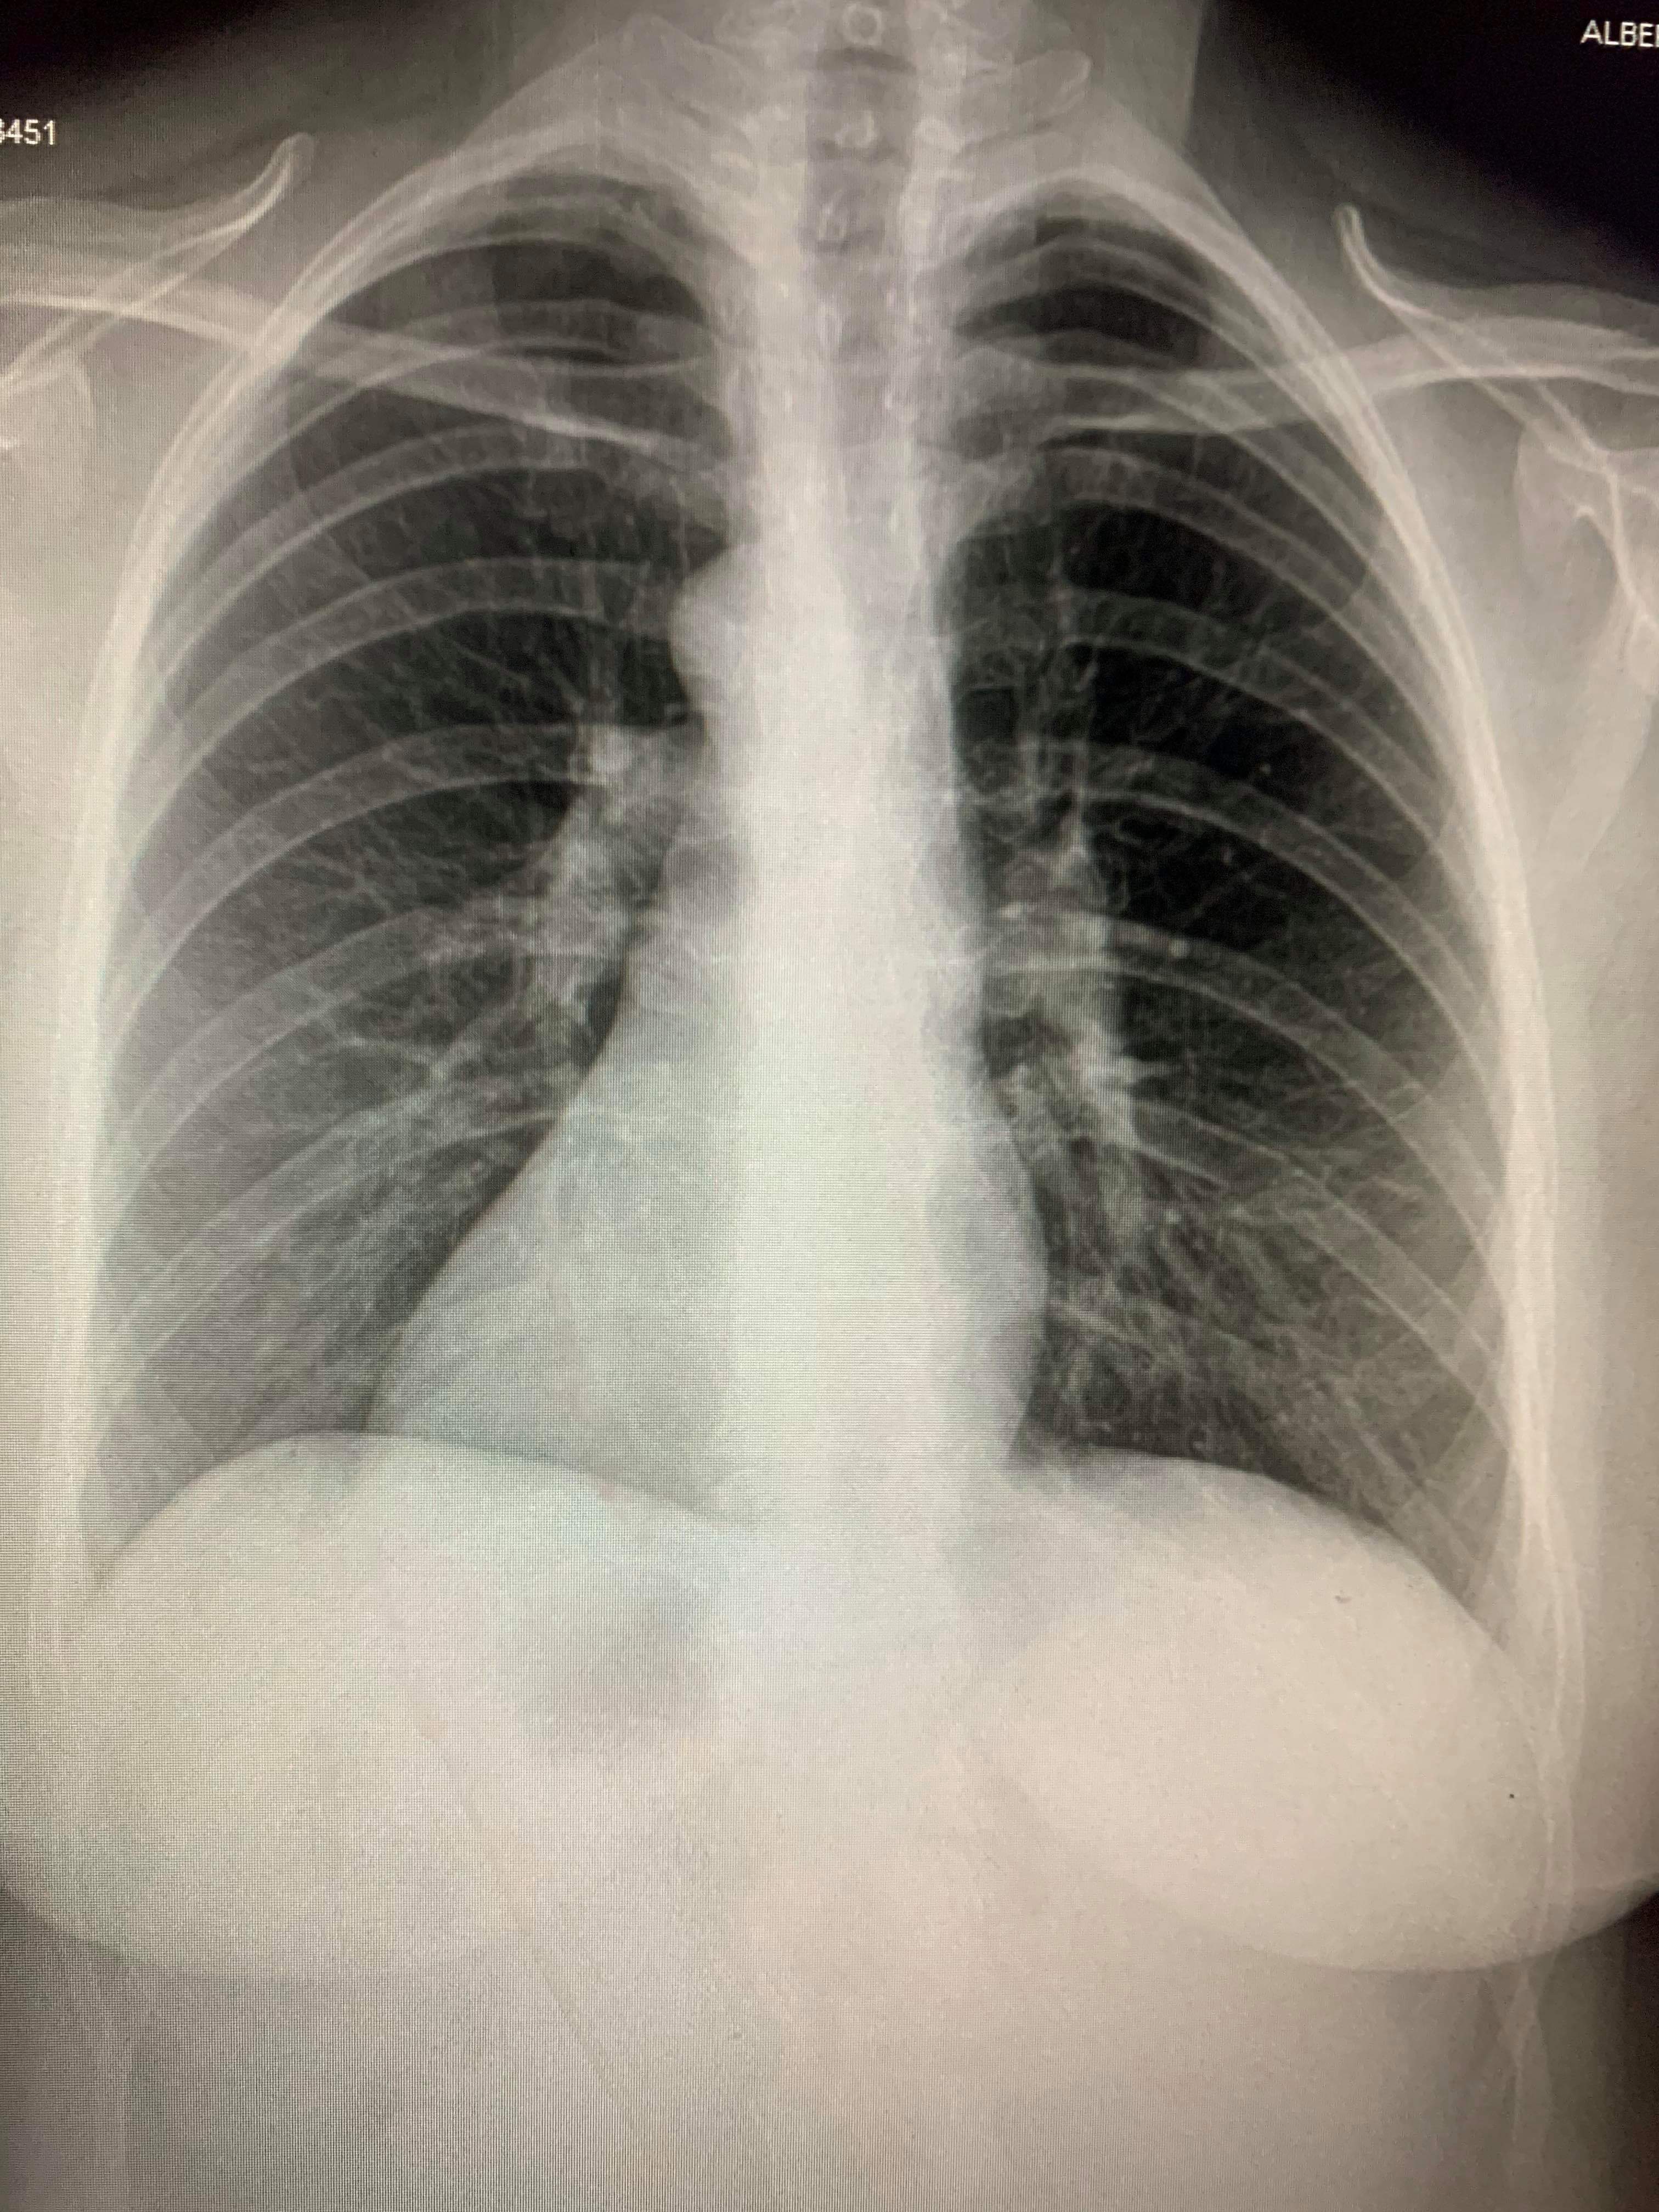

38 year old female. 1 week apart. She is intubated and has about a 20% of living. This was my latest patient.

I love my Mariner baseball more than just about anything, but I do not wish this virus on anyone, much less any of us. It's hard staring at all these people daily who are suffering praying they you don't wind up getting infected and then have to not only be quarantined off from you're job, but youre own family. Its shitty man, it's just shitty.

Attachments

received_1059909764393004.jpeg

received_567218973887429.jpeg